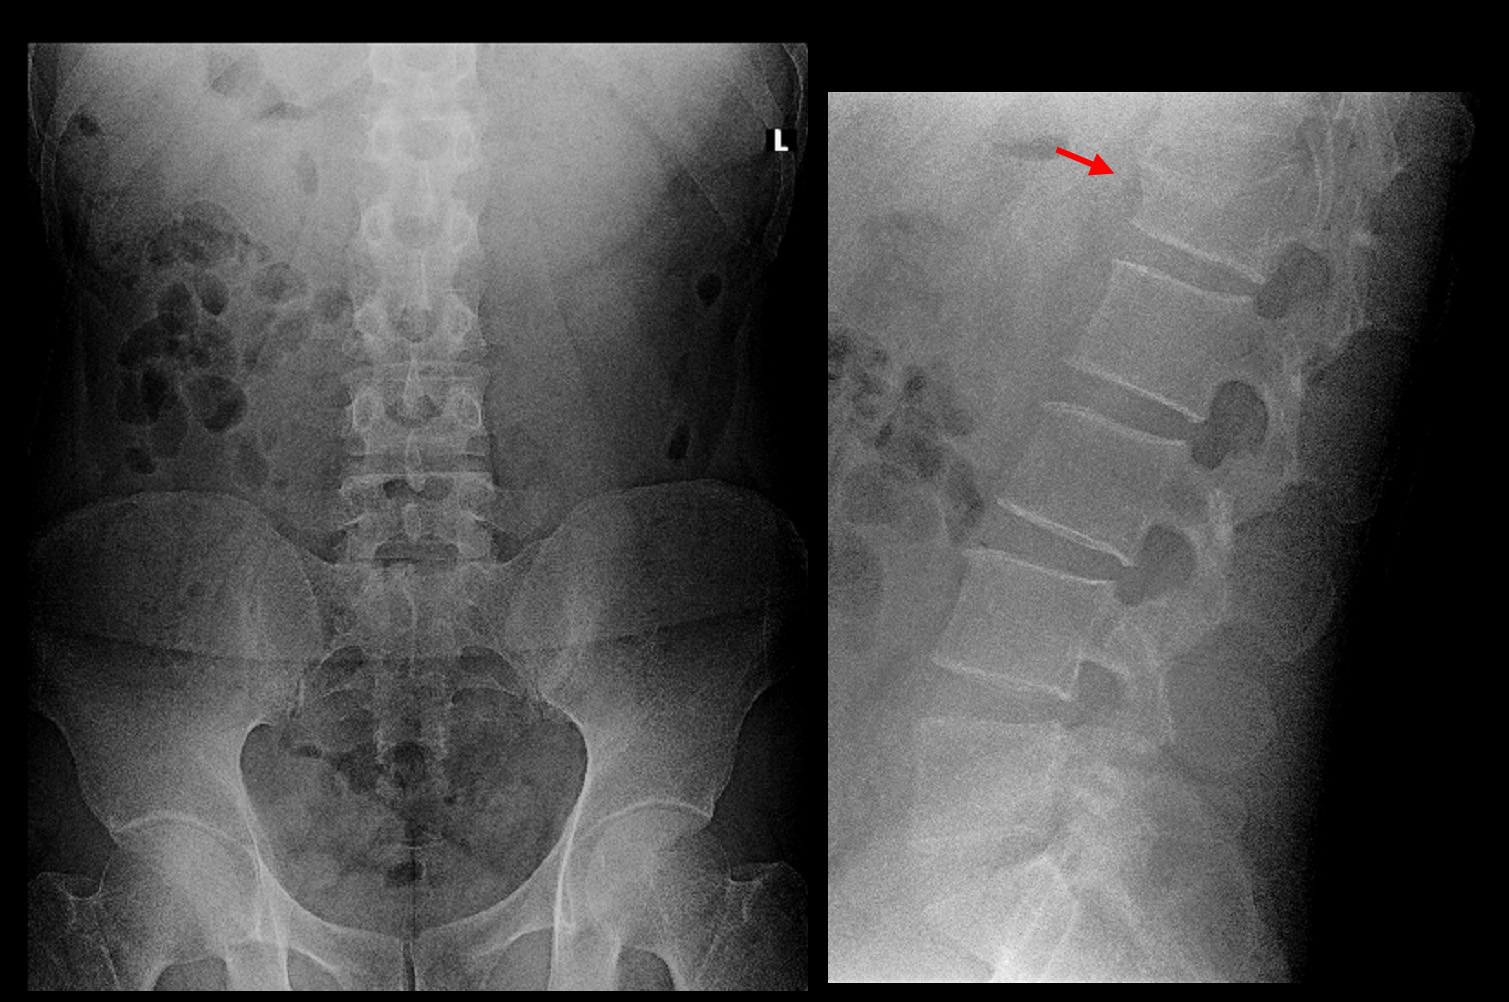

82才男 Xp2.jpg

オレンジ丸の領域が第12胸椎圧迫骨折受傷時の腰痛で、4月15日に相談された時の腰痛は赤丸領域となります。

44才男 Xp2.jpg

腰椎のレントゲン像では坐骨神経痛を起こすような所見は確認できません。しかし、第1腰椎の上縁が陥凹しています。Sさんは10年前の平成25年1月24日にスノーボードで尻もちをついて第1腰椎の圧迫骨折を受傷し、当院で加療していたのです。